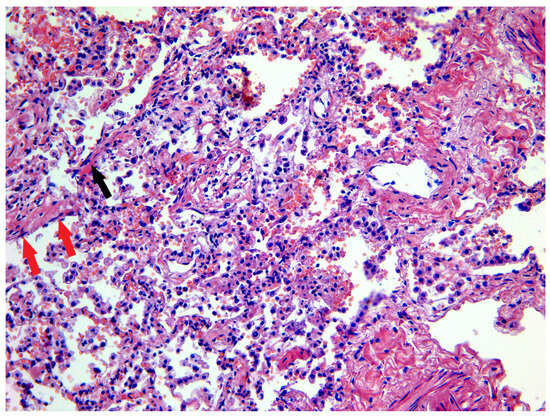

3.1. Lung and Upper Airway Findings

| Pulmonary capillary congestion | 22/22 | 100 |

| Hyaline membranes | 17/22 | 77 |

| Fibrin in alveoli | 18/22 | 81 |

| Interstitial edema | 9/22 | 41 |

| Metaplasia of alveolar epithelium | 6/22 | 27 |

| Desquamation of alveolar epithelium | 19/22 | 86 |

| Pulmonary infarction | 2/22 | 9 |

| Microvascular thrombosis | 16/22 | 72 |

| Giant cells | 8/22 | 36 |

| Hyperplasia of Type II alveolocytes | 10/22 | 45 |

| Pleuritis with fibrin | 2/22 | 9 |

| Amyloid deposits | 8/22 | 36 |